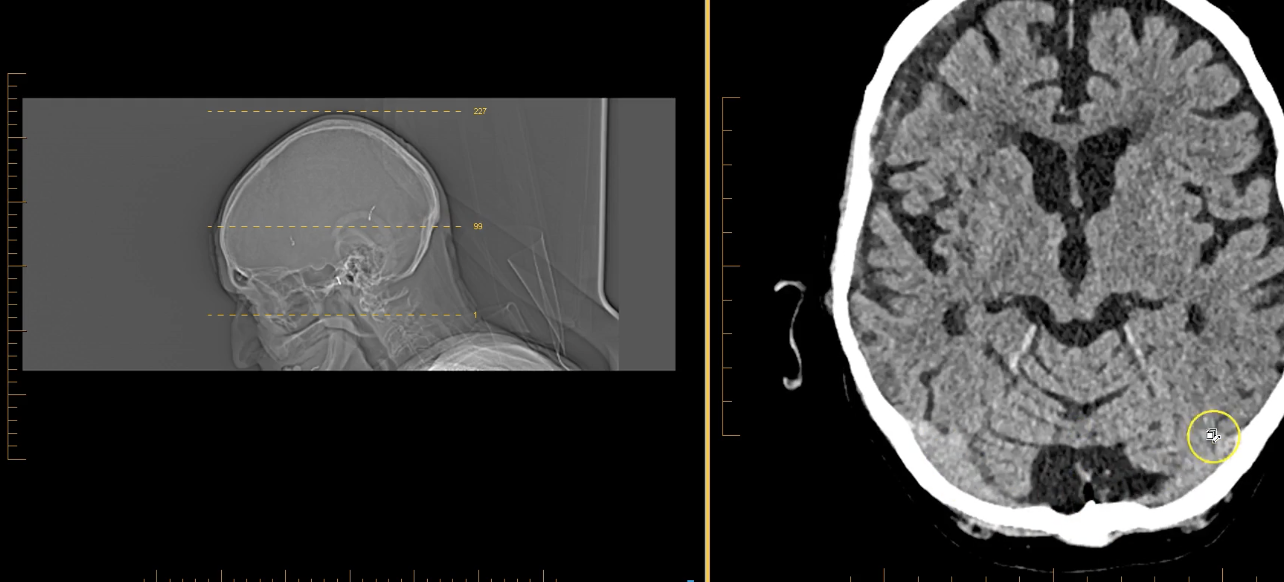

term image

pineal gland- hyperdense. part of endocrine system. secrenes melatonin